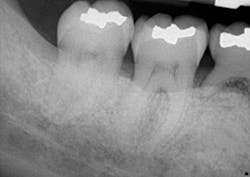

A clinical periodontal and radiographic assessment is completed. Although there is moderate bone loss in all four quadrants, his periodontal status is stable with the exceptions of Nos. 18 and 31 distal (figures 1 and 2). Both areas reveal direct distal probing depths of at least 10 mm and radiographic infrabony distal defects.

Figure 1: No. 18